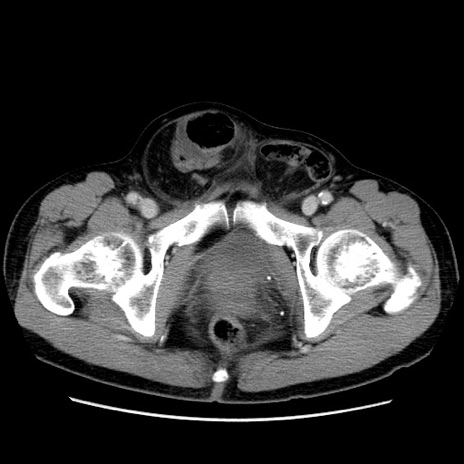

症例34(横断像)

【症例】60歳代 男性

【主訴】右鼠径部膨隆

【現病歴】1年程前より右鼠径部膨隆あり。自己にて還納可能だったため放置していた。3時間前より右鼠径部の脱出を認め、還納困難となり受診。

【既往歴】高血圧

【身体所見】右鼠径部に小児頭大の膨隆あり。弾性硬であり、用手還納は困難。左鼠径部にも膨隆を認める。脱出はなし。